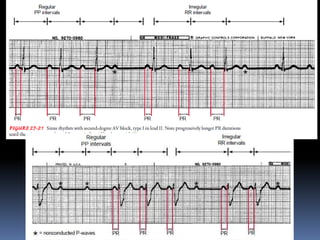

2nd degree AB block . Progressive prolongation of PR- interval followed by a drop

beat ( nonconducted P ) . Wenkebach’s type ( Mobitz’s type-1 ).

2nd degree ABblock . Progressive prolongation of PR- interval followed by a drop beat ( nonconducted P ) . Wenkebach’s type ( Mobitz’s type-1 ). 2nd degree AV block. 2:1 AV block.Whether it is Mobitz type 1 or 2 , can’t be differentiate.

Third Degree A-Vblock PP regular RR regular PR( AV dissociation)

• 52.